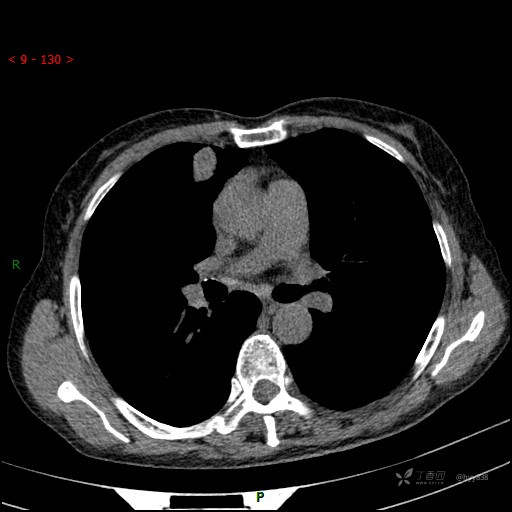

胸部CT平扫